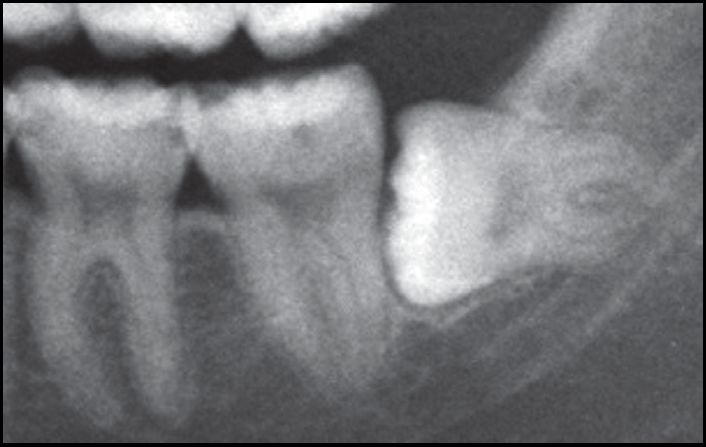

同样的阻生智齿的不同拔除方法

A.水平智齿仅露出远中牙冠

B.X线显示阻生智齿水平中位

C.直接分牙法并未切开、翻瓣、去骨拔除

D.智齿拔除,牙槽窝完好